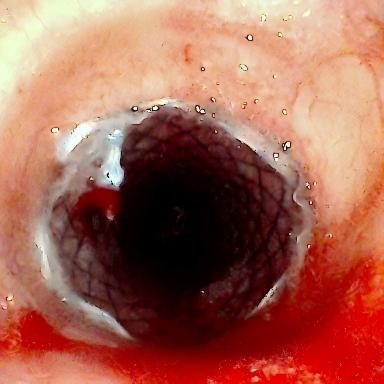

患者为75岁女性,因“反复咳嗽咳痰、气促10余年,加重3月”,于3月3日入住湘雅三医院呼吸与危重症医学科。入院时患者呼吸困难症状严重,CT检查提示气道存在严重狭窄,随时面临窒息风险。经管床医生杨红辉评估,患者气管狭窄情况复杂:最狭窄处管腔直径仅剩1-3mm,科室最细的4.0mm支气管镜也无法通过;狭窄位置极低,下缘距隆突仅1.6cm,意味着无法通过气管切开绕过病灶;狭窄处周围组织的CT值高达60-70Hu且无强化,因而直接植入支架存在无法撑开或加重堵塞的风险;同时,患者无法耐受全身麻醉,仅能采用利多卡因进行表面麻醉,操作难度较大。

方案确定后,ICU团队何智辉、邢伟、邓龙天为患者建立体外生命通道;呼吸介入团队孟婕、杨红辉、刘建明、邹丽君、贺一峻等通过球囊对狭窄部位进行预扩张,随后在距隆突仅1.6cm的低位气道精准植入支架。支架贴合良好,气道顺利开通,全程操作约1.5小时。患者当晚撤离ECMO,次日从ICU转回普通病房。后续肺泡灌洗液检测显示,患者大气道狭窄的原因为气管结核导致的瘢痕性狭窄。